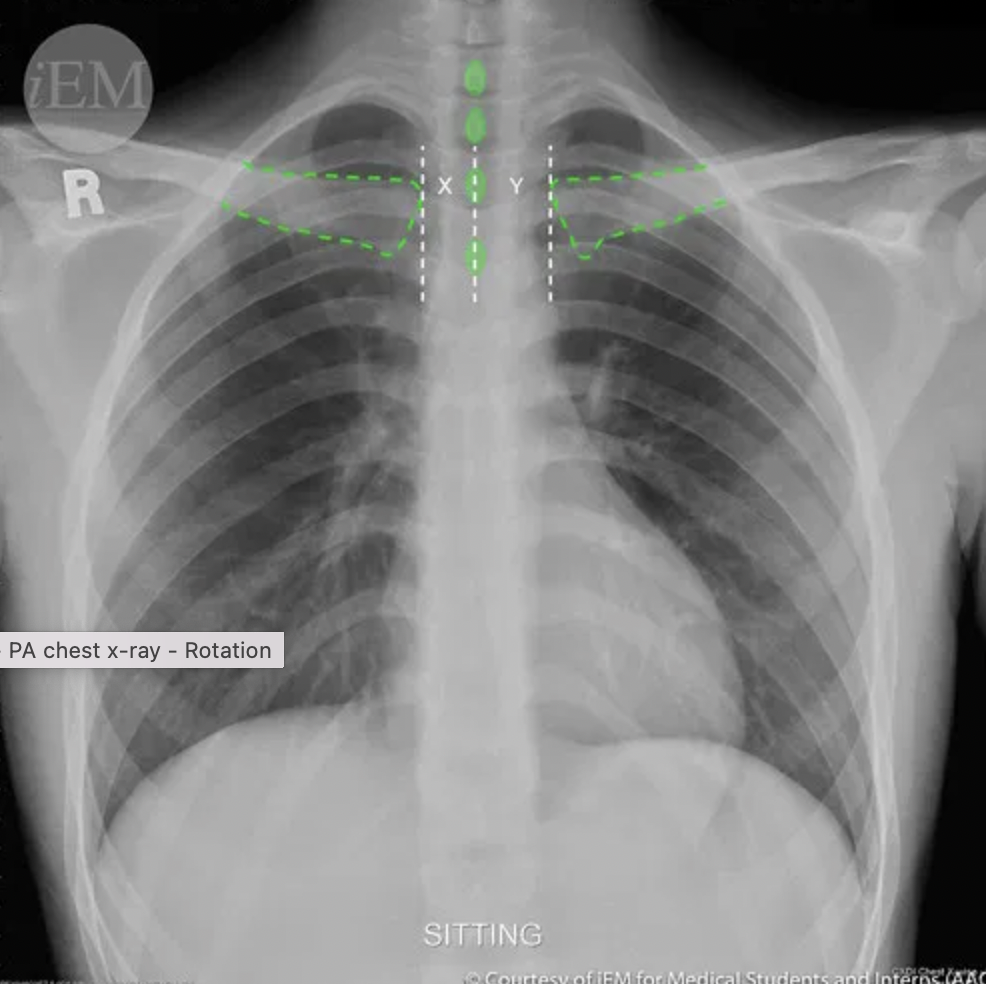

What does rotation in CXR refer to?

refers to poor positioning – the patient is turned and not straight which can make interpretation difficult

How can you assess rotation in a CXR?

1. Medial aspect of each clavicle should be equidistance from the spinous processes

2. Spinous processes should be vertically orientated against the vertebral bodies

In this CXR, which way is the patient rotated?

How do you know?

A

Patient is rotated to the left

Anterior structures move the same direction as rotation → the clavicle/spinous process width is increased on the side to which the patient is rotated